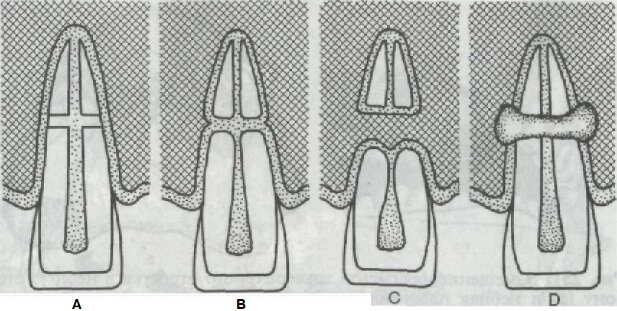

Основным способом лечения переломов корня является укрепление зуба при помощи назубной шины. Заживление переломов зубов происходит через 1 1/2—2 мес. Выделяют 4 типа заживления переломов (рис. 250).

Рис. 250. Типы заживления перелома корня зуба (по Pindborg). Объяснение в тексте.

Тип А: фрагменты тесно сопоставлены друг с другом, заживление завершается минерализацией тканей корня зуба.

Тип В: заживление происходит с образованием псевдоартроза. Щель по линии перелома заполняется соединительной тканью. На рентгенограмме видна необызвествленная полоса между фрагментами.

Тип С: между фрагментами врастают соединительная ткань и костная ткань. На рентгенограмме видна кость между фрагментами.

Тип D: промежуток между фрагментами заполняется грануляционной тканью: либо из воспаленной пульпы, либо из ткани десен. Тип заживления зависит от положения фрагментов, иммобилизации зубов, жизнеспособности пульпы.